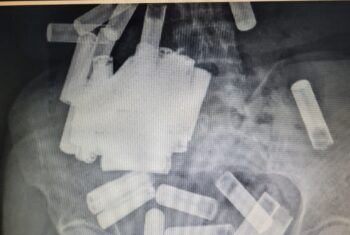

Los médicos en Irlanda extrajeron 55 pilas del intestino y el estómago de una mujer después de que se las tragó en un aparente acto de autolesión deliberada. La mujer, de 66 años, fue tratada en el Hospital Universitario de St. Vincent en Dublín después de ingerir un «número desconocido» inicialmente de pilas, según un informe […]